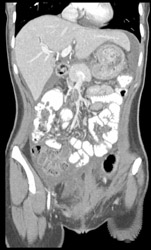

Aortic Dissection